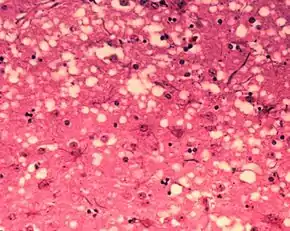

Brain tissue of a cow with BSE showing the typical microscopic "holes" in the grey matter

Diagnosis of BSE continues to be a practical problem. It has an incubation period of months to years, during which no signs are noticed, though the pathway of converting the normal brain prion protein (PrP) into the toxic, disease-related PrPSc form has started. At present, virtually no way is known to detect PrPSc reliably except by examining post mortem brain tissue using neuropathological and immunohistochemical methods. Accumulation of the abnormally folded PrPSc form of PrP is a characteristic of the disease, but it is present at very low levels in easily accessible body fluids such as blood or urine. Researchers have tried to develop methods to measure PrPSc, but no methods for use in materials such as blood have been accepted fully.

The traditional method of diagnosis relies on histopathological examination of the medulla oblongata of the brain, and other tissues, post mortem. Immunohistochemistry can be used to demonstrate prion protein accumulation.[24]